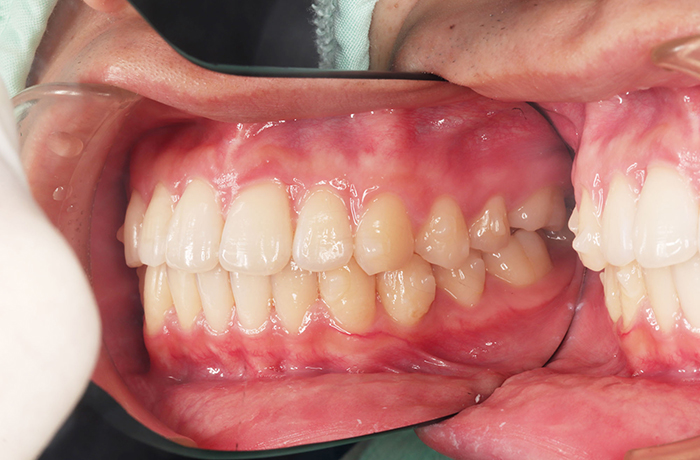

I様

治療前

年齢 34歳

性別 男性

治療名称 マウスピース型カスタムメイド矯正歯科装置(インビザライン)・コンプリヘンシブパッケージ(フルパッケージ)

総額治療費用 770,000円(税込) 金額備考 検査・診断料33,000円含む

治療期間 8か月 通院頻度など 40日ごと

その他治療に関する情報 1枚につき10日装着を指示しました。

治療内容

患者の症状 上顎前歯の凸凹

治療方法 非抜歯で、マウスピース型カスタムメイド矯正歯科装置による矯正

治療結果 歯並び、咬み合わせが良くなりました。

その他治療に関する情報 歯並びをより良くするために追加でアライナーを発注しました。

治療を行う上での注意点

リスク/副作用 スペース不足を解消するために歯と歯の間をわずかに削合しました。